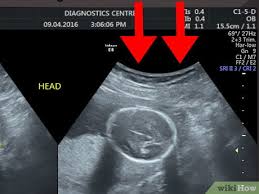

Cara Membaca Foto Usg 8 Langkah Dengan Gambar Wikihow

Cara Membaca Foto Usg 8 Langkah Dengan Gambar Wikihow from www.wikihow.com